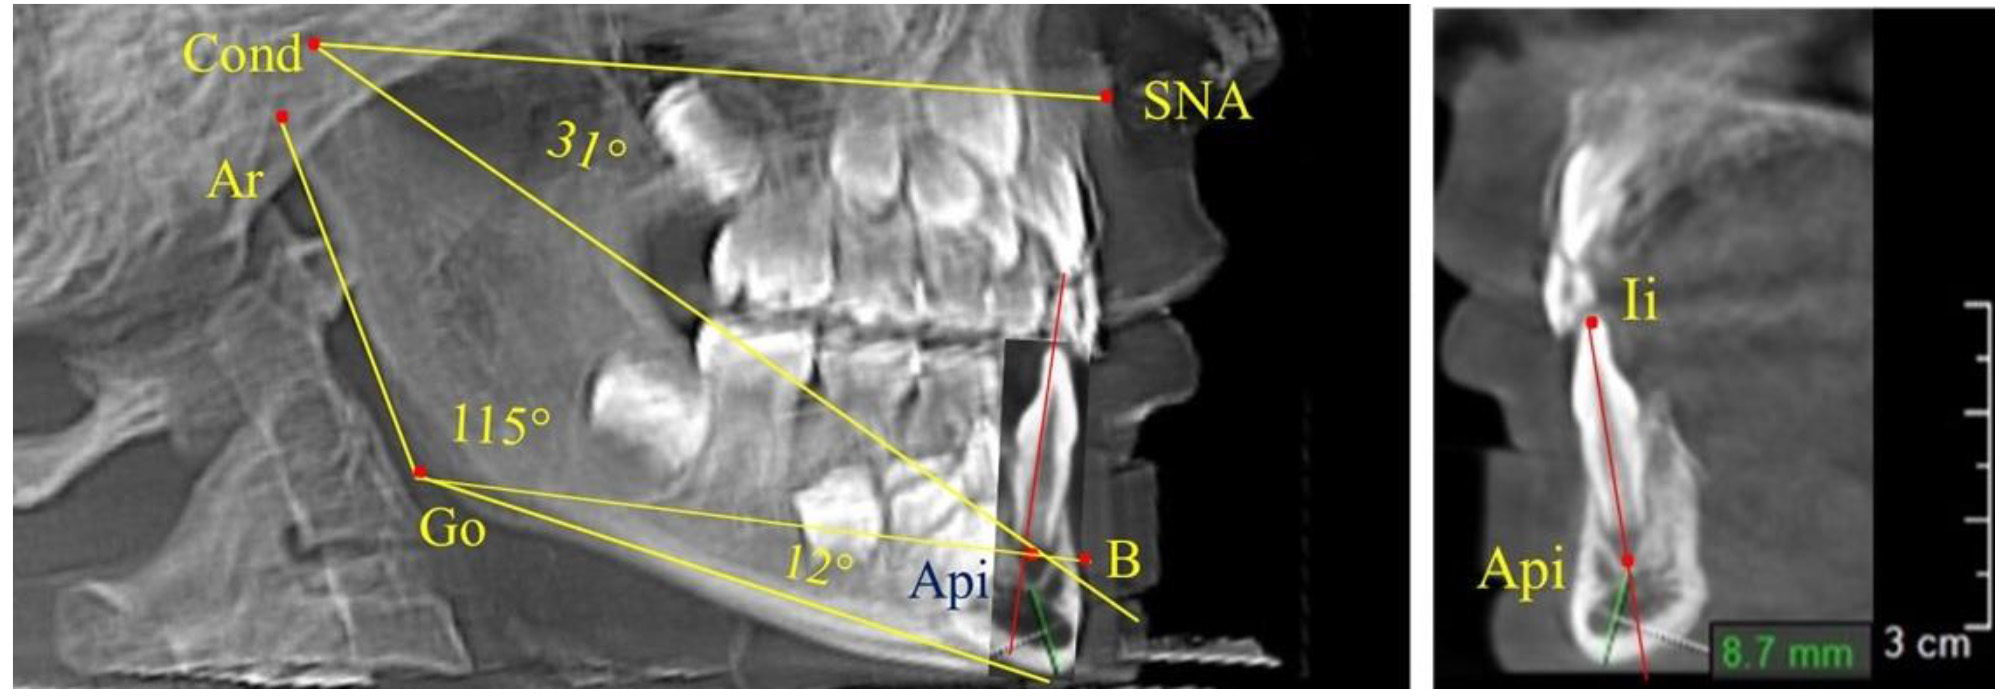

Через апикальную точку нижнего резца от суставной точки проводили линию Cond-Api, которая с линией Cond-SNA образовывала угол гнатический части лица SNA-Cond-Api, используемый для оценки ее основных параметров.

Кроме того, угол нижней челюсти Ar-Go-Me линией Go-Api делили на две составляющие. Верхняя часть угла Ar-Go-Api определяла значение альвеолярного нижнечелюстного угла, а угол Api-Go-Me определял особенности части тела нижней челюсти (рис. 1).

Особенность анализа телерентгенограммы в периоде сменного прикуса заключалась в том, что наслоение зачатков постоянных зубов затрудняло определение апикальной точки нижнего резца. В подобных случаях использовали метод совмещенного анализа телерентгенограммы с фрагментом томограммы, на котором, также как и на телерентгенограмме, определяли положение резцовой и апикальной точек с построением условной вертикали, которая служила ориентиром для совмещения фрагментов (рис. 2).

Рис. 2. Особенности совмещения телерентгенограммы с фрагментом томограммы в сменном прикусе